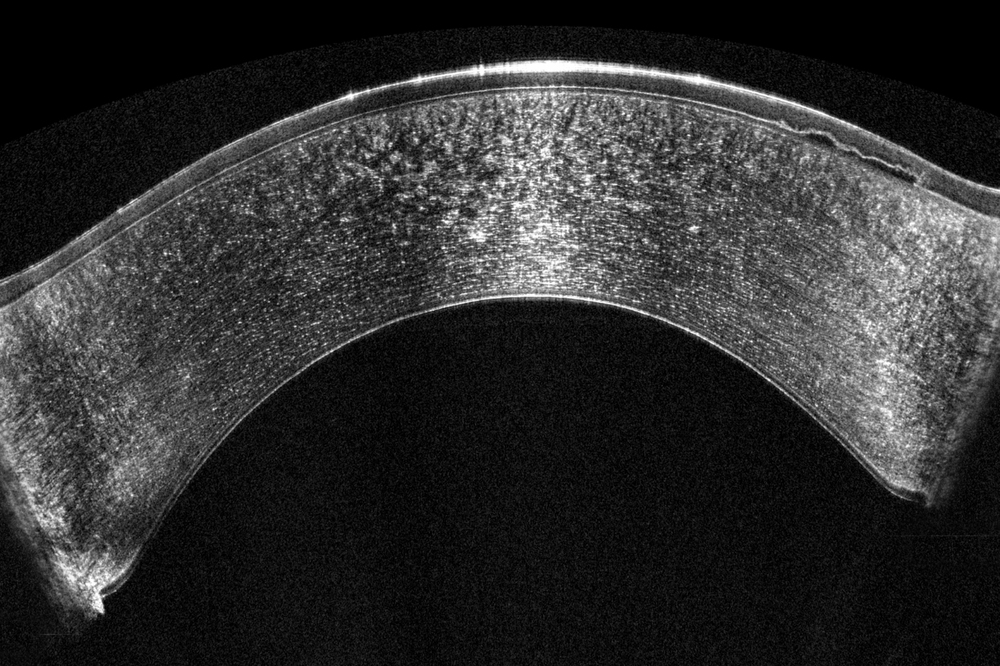

Hoge-resolutie OCT-technologie maakt gedetailleerde visualisatie van de corneale structuren mogelijk, inclusief nauwkeurige meting van de epitheliale dikte. Deze meting is cruciaal voor de vroege detectie van corneale ectasie. Epitheliale diktemapping ondersteunt bovendien de chirurgische planning, wat bijdraagt aan optimale resultaten van refractiechirurgie. OCT-beeldvorming is bovendien essentieel voor:

- Ultra hoge resolutie over het gehele hoornvlies

- Uniek groothoek pericentrisch scansysteem

Door Scheimpflug-technologie en OCT te combineren ontstaat een volledig beeld: Scheimpflug toont lichtverstrooiende structuren in het voorste oogsegment met blauw licht, terwijl OCT ongeëvenaarde details geeft. Beide metingen worden gelijktijdig uitgevoerd op exact dezelfde locaties, wat directe en gedetailleerde visualisatie van alle afwijkingen mogelijk maakt.

- OCT geeft gedetailleerde structuren